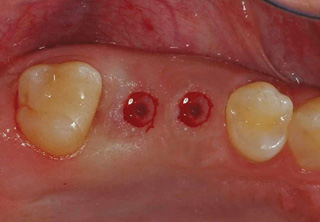

흔히 "네비게이션 임플란트"라고 말하는 컴퓨터 분석을 이용한 임플란트란?

컴퓨터 분석을 이용한 임플란트는 3차원 영상 분석을 통하여 적절한

임플란트의 식립 위치와 방향 등을 결정하여 치료계획을 수립하고,

이를 토대로 개별 맞춤 수술유도장치를 제작하여 시술하는 방법입니다.

일반적으로 잇몸을 절개하지 않고 시술하여 수술시간이 짧으며, 수술 후 통증이나 붓기, 출혈이 적은 장점이 있습니다.

시술 전 3D영상장치 등을 통한 진단계획과

모의 수술을 통해 환자의 골조직과 신경관의

위치 등을 파악하여 명확한 치료 계획을

수립하고 개별 맞춤 수술유도장치를

사용하므로 신경 손상 및 부정확한 임플란트

시술의 위험이 적습니다.